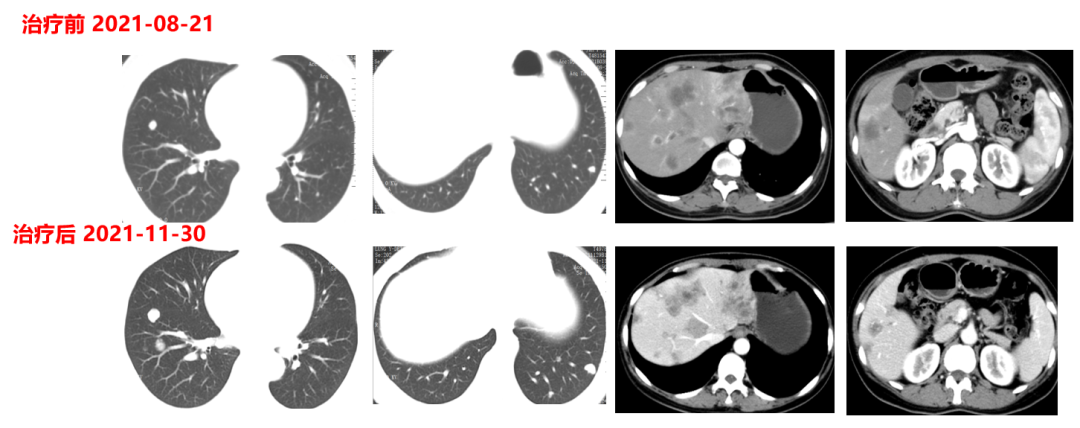

于2021.04.17行“FOLFOX6”方案化疗1周期,行“奥沙利铂”化疗时,出现严重过敏。因患者基因状态为RAS,BRAF野生型,第2周期始给予“FOLFIRI+西妥昔单抗”,在治疗过程中,肿瘤标志物持续下降,影像学也显示肝脏病灶明显缩小。疗效评价PR,在2021-09-25在局麻DSA下行“肝动脉造影并化疗灌注栓塞术”。

肿瘤初次进展(2021-11-30)

患者于2021年11月30号复查时,肺上病灶增大增多,肝脏病灶稍增大,肿瘤标志物增高,整体疗效评价PD,考虑一线治疗进展。